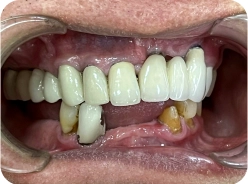

ANH TẤN DŨNG

VIỆT KIỀU MỸ

Phương án: Cấy ghép Implant All On 4 cho 2 hàm

Loại trụ: Implant Mis C1 Đức -